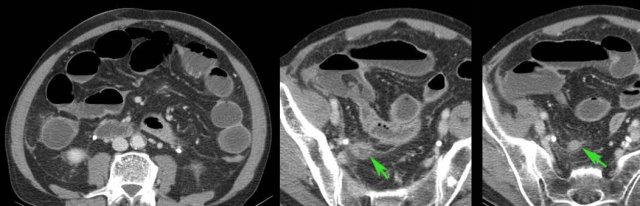

This obese lady presented with RLQ pain, a CRP of 80 and a normal serum amylase.

US identified a 6 mm appendix (arrows) with severe local tenderness.

CT scan revealed acute pancreatitis with retroperitoneal fluid (*) descending to the RLQ, explaining the patient’s symptoms mimicking appendicitis.

The pancreatic exudate (*) approaches the appendix (arrow) closely.